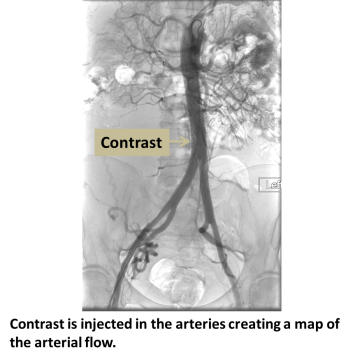

An interventional radiologist accesses an artery, usually the femoral artery at the groin. Small catheters are passed into the artery of interest, and contrast injection and X-rays are used to evaluate the arteries. If needed, treatment with angioplasty or stent can be performed concurrently.